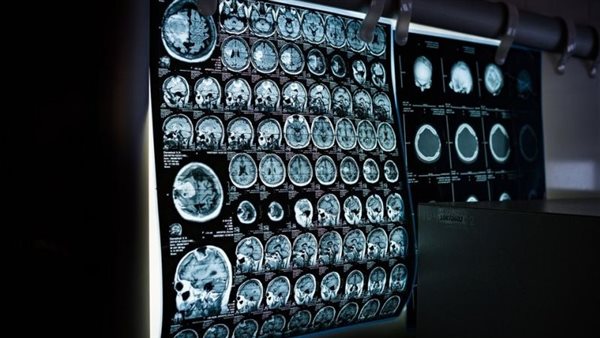

دراسة تربط بين انخفاض مستويات هرمون السعادة في الدماغ وانخفاض وظائف المخ

أفادت دراسة جديدة، بأن فقدان هرمون السيروتونين السعادة في الدماغ، قد يلعب دورًا في تراجع وظائف المخ مع تقدم الشخص في العمر، والدراسة نشرت في مجلة مرض الزهايمر.

شملت الدراسة مشاركة أشخاص يعانون من ضعف إدراكي خفيف و45 شخصًا بالغًا يتمتعون بصحة جيدة تبلغ أعمارهم 55 عامًا أو أكثر، وحلل الباحثون التغيرات في بنية الدماغ بين عامي 2009 و2022.

وجد باحثون، أن الأشخاص الذين يعانون من ضعف إدراكي معتدل لديهم مستويات أقل من السيروتونين بنسبة تصل إلى 25٪ مقارنة بالأشخاص الأصحاء في المناطق الرئيسية من الدماغ المرتبطة بالذاكرة وحل المشكلات والعاطفة.

وكان المرضى لديهم أيضًا مستويات أعلى من أميلويد بيتا، وهو البروتين الذي يشكل كتلًا سامة في أدمغة مرضى الزهايمر.